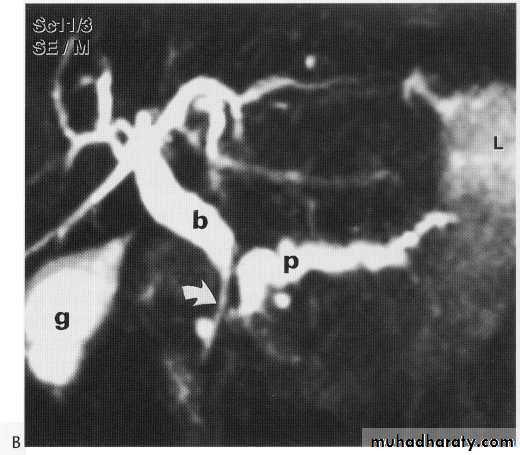

MRCP + ERCP